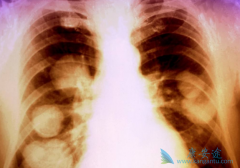

随着现代医学对肺癌的不断深入了解,越来越多的治疗方法被应用到临床治疗中,传统的手术、放化疗手段不断优化,新型的靶向治疗、免疫疗法层出不穷。因此肺癌的治疗也逐步进入了精准治疗时代,尤其是有特定基因突变的晚期肺癌患者,相应靶向药物治疗是首 ...